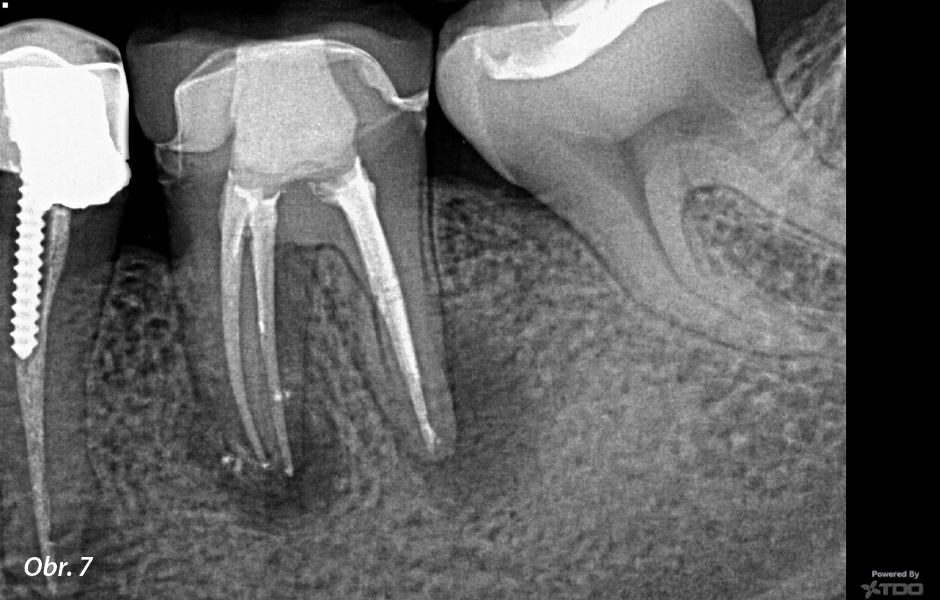

Co se stane, když ošetříte kořenový kanálek a léze se nehojí? Nejprve si musíte položit otázku: „Opravdu jsem úplně dezinfikoval zub? Našel jsem všechny kanálky a dostal jsem se na konec každého kanálku?“ Pamatujte, že milimetr je v endodontickém světě míle a pokud se nedostanete až k samotnému konci kanálku, stále zde mohou zůstat nějaké bakterie.

Nejprve tedy doporučuji skutečně posoudit váš dezinfekční protokol a mým návrhem bude vždy nejprve reendodoncie! Když zubaři často nedokážou vysvětlit, proč kořenový kanálek selhává, tak si automaticky myslí, že je zub prasklý, a začnou přemýšlet o nahrazení zubu. Ale to může být chybné! Nikdo není dokonalý a dokonce i ti nejlepší z nás musí provádět reendodoncie svých vlastních případů (zeptejte se mě, jak to vím!). Žádám vás tedy, abyste dali zubům šanci, a to obvykle znamená nejprve reendodoncii!

Pokud příznaky přetrvávají i po reendodoncii, přemýšlejte o dalších možnostech, jako je apexektomie. Existuje spousta anatomických studií, které ukazují, že v posledních 3 mm kořene mohou existovat rozsáhlé apikální ramifikace a isthmy. Pokud se tyto oblasti obtížně čistí, jedinou možností je fyzicky je odstranit apexektomií. Díky Bohu, že s tímto postupem přišli, protože nám umožňuje zachránit ještě více zubů.

Pamatujte, že apexektomie není něco, do čeho chcete jen tak skočit; chcete nejprve vyčerpat všechny své ortográdní možnosti. Při plánování léčby je třeba mít na paměti, že odstranění apexu ošetří pouze posledních 6 mm kořene, takže pokud máte podezření, že v celém kořeni jsou bakterie, musíte provést nejprve reendodontické ošetření. Vidíte, kam tím směřuji?